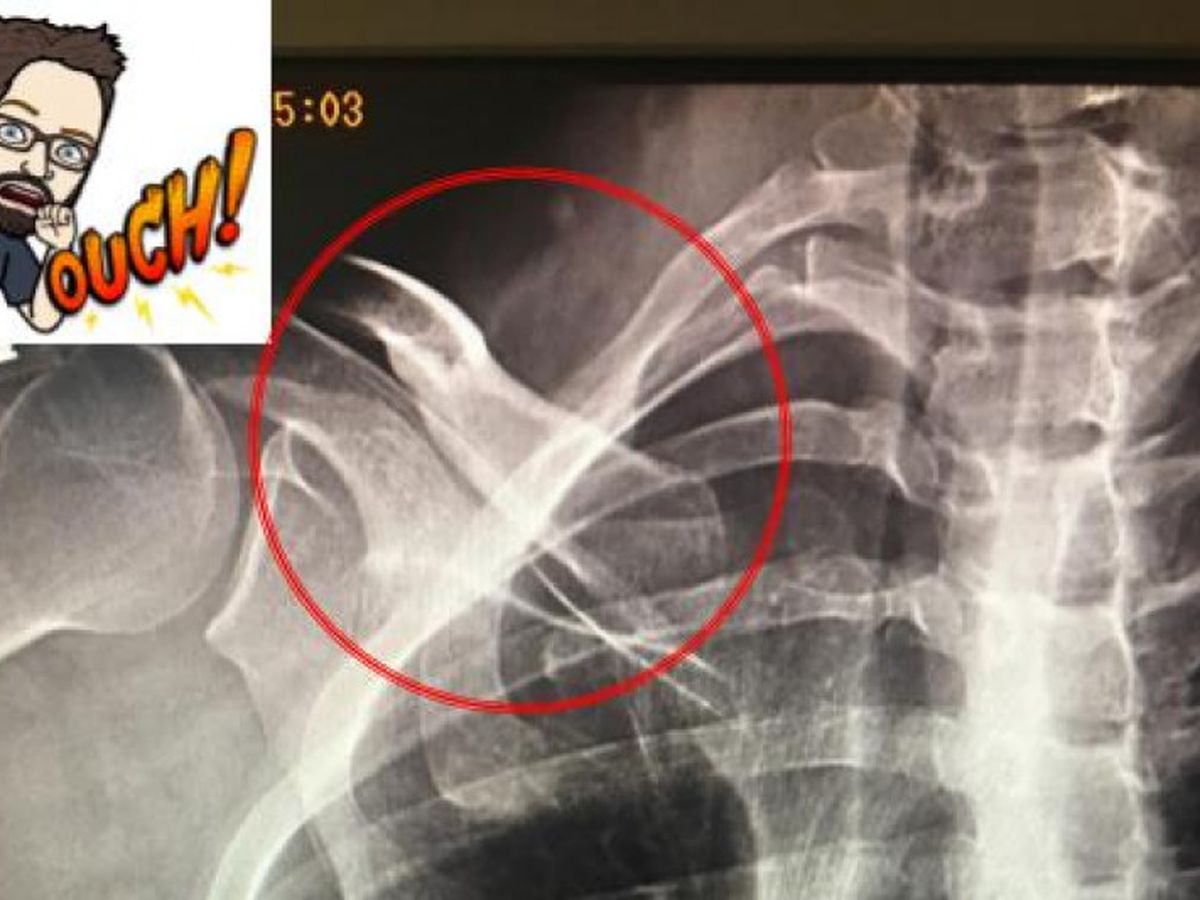

Basically, I was born with a extra cervical rib (see below)